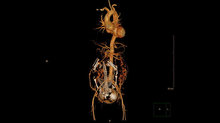

36歲劉小姐懷孕9個月,日前無預警劇烈胸痛、瀕臨休克,被緊急送至台北慈濟醫院急診。經心臟外科蔡貴棟醫師診斷其患有7公分大的主動脈根部動脈瘤,因主動脈瘤內膜裂開導致A型主動脈剝離。

為全力保住母子倆,蔡貴棟醫師與醫療團隊審慎評估,孕婦幼年時期曾做過主動脈瓣膜修補手術,術後沾黏或可延遲主動脈剝離的出血時間,因此決定先取出胎兒,而後執行升主動脈及主動脈根部動脈瘤置換手術。手術時間逾16小時,術後劉小姐入住加護病房觀察待病情穩定後,轉至普通病房復健1周,出院後定期回診追蹤,順利回歸原有家庭生活。

產後的修復期間,劉小姐病情急遽惡化,2度瀕臨死亡,醫療團隊緊急為其裝置葉克膜體外循環心肺支持系與人工心肺機,而後針對劉小姐的主動脈根部動脈瘤及主動脈剝離2種病症,執行逾16小時的升主動脈及主動脈根部動脈瘤同時置換手術。